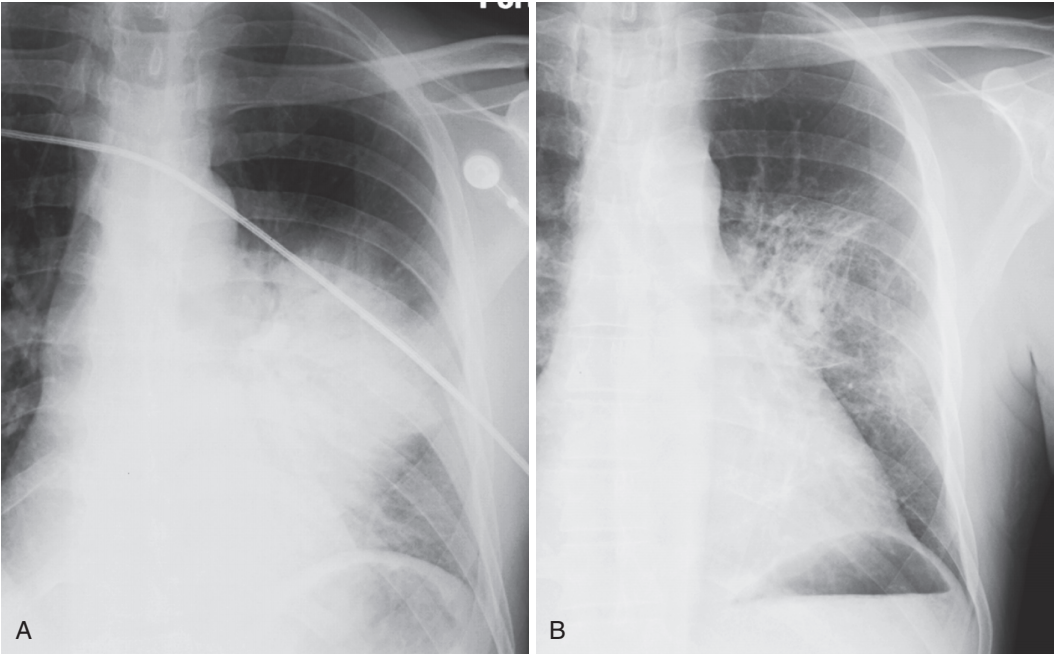

- La radiografía de tórax de control se solicita a las 6-8 semanas de finalizado el tratamiento a los pacientes con evolución clínica prolongada y en sujetos fumadores para descartar el cáncer pulmonar; no se justificaría en pacientes con evolución clínica favorable y sin factores de riesgo. Si se pesquisan signos de alarma (compromiso del estado general, rechazo alimentario, fiebre prolongada, dificultad respiratoria progresiva, compromiso de conciencia o inestabilidad hemodinámica) se debe referir al hospital

- La neumonía, especialmente la neumonía neumocócica, puede resolverse en 2-3 días si el microorganismo causal es sensible al antibiótico administrado. La mayor parte de las neumonías suelen resolverse desde dentro (vacuolización), con la desaparición gradual de forma parcheada en el transcurso de varios días o semanas. Si una neumonía no se resuelve al cabo de varias semanas, hay que considerar la posibilidad de una lesión obstructiva subyacente, como un tumor que impide el drenaje adecuado de la porción del pulmón afectada. La TC torácica puede ser útil para mostrar la lesión obstructiva.